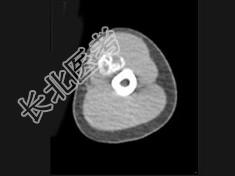

- 单项选择题男,21岁, 左上肢有外伤史,现感局部疼痛, 可扪及包块,结合图像, 最可能的诊断是 ( )

A、骨外骨肉瘤

B、骨外软骨肉瘤

C、皮质旁骨肉瘤

D、邻皮质软骨瘤

E、骨化性肌炎